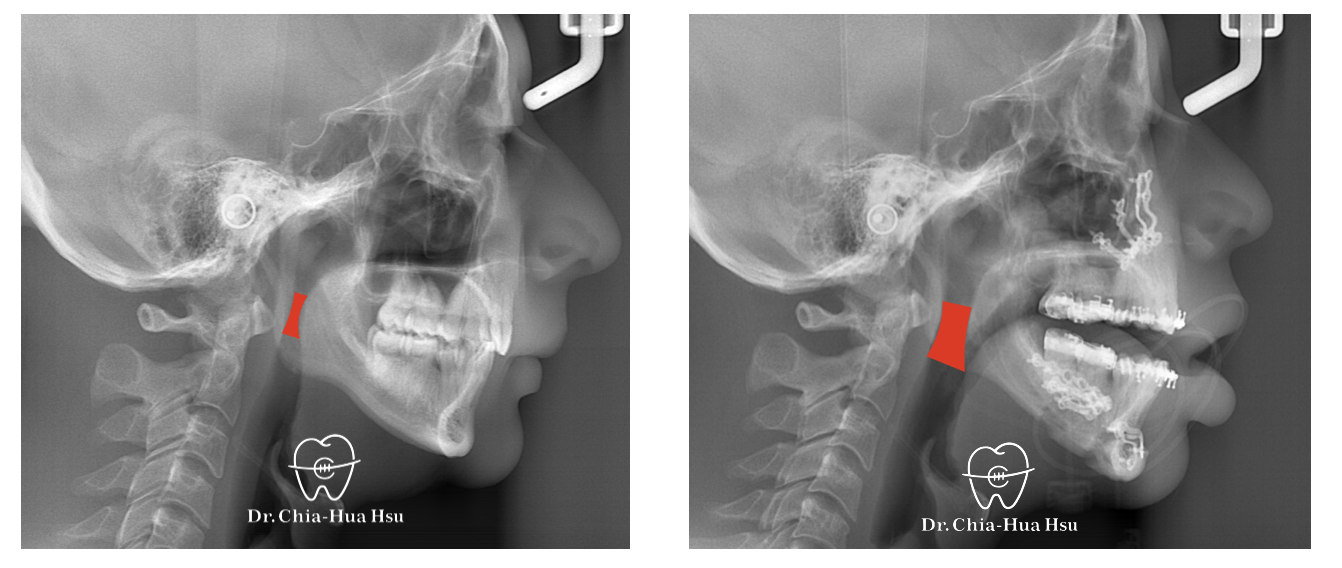

治療過程:患者有下顎後縮合併有睡眠呼吸中止症,接受了雙顎前移手術。

左圖為治療前之側顱X光攝影,右圖為手術後一天拍攝之側顱X光攝影,明顯可見其呼吸道狹窄獲得改善,患者術後睡眠品質亦大幅改善。